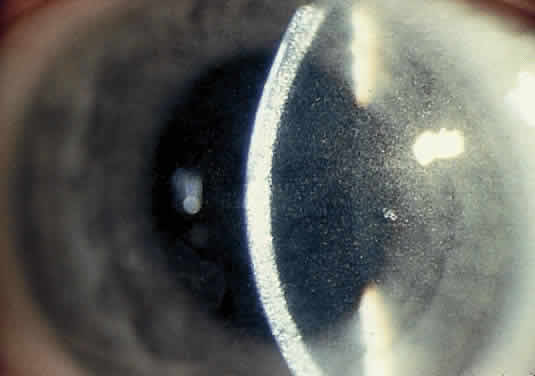

Corneal deposits appear as a layer of homogeneously distributed, fusiform or needle-shaped, iridescent crystals situated in the stroma beneath the epithelium. In the infantile form, anterior crystal deposition begins early in life (between 6 and 15 months of age) and proceeds posteriorly as the patient ages; deposition advances more rapidly in the periphery. The anterior location of the crystals may be associated with recurrent erosions.33 The depth of the stromal deposition and the density of crystals is always greater peripherally than centrally. More and larger crystals occur in the superficial stroma. No visual impairment occurs at this early stage. By the age of 7 years, most patients have crystals, either within or on the endothelial surface34,35; markedly decreased corneal sensitivity is also present.36 The spherical contrast sensitivity function is significantly lower in infantile cystinosis than in age-matched controls.37 The conjunctiva has a ground-glass appearance. Polychromatic, polymorphic, rectangular, or rhomboidal crystals can be seen with the biomicroscope. The uvea contains an abundance of polymorphous crystals. Clinically, these can be seen as glistening dots on the surface of the iris. Thickened iris stroma and posterior synechiae may occur; pupillary block glaucoma38 also has been reported. The entire uvea has polymorphic crystal deposition, most heavily in the choroid. The sclera also has crystal deposition. The retinal abnormality consists of a generalized depigmentation that may assume a patchy pattern. At first the pigmentary disturbance tends to be peripheral, but it progresses with age. Macular abnormalities have been observed.39 Intracellular crystals also have been seen in the retinal pigment epithelial cells during electron microscopy. DIAGNOSIS. The ocular findings of cystinosis are sufficiently unique and characteristic to form the basis for a diagnosis of this disease. A specific diagnosis of cystinosis can be made by assaying for cystine in biopsied conjunctiva.40 Conjunctival biopsy is a simple and benign technique that may provide the diagnosis for this and other inborn errors of metabolism. DIFFERENTIAL DIAGNOSES. Polychromatic corneal crystals similar to those in cystinosis also may be seen in multiple myeloma,41 Schnyder's crystalline dystrophy, Bietti's crystalline dystrophy, gout, and chrysiasis. MANAGEMENT. The results of therapy with penicillamine and a cystine-free diet for infantile nephropathy have been disappointing.29 Oral cysteamine is the only available treatment for the nephropathy of infantile cystinosis. The cystine depletion that occurs through the formation of cystine-cysteamine-mixed disulfide42,43 apparently helps stabilize glomerular function and also improves growth and development.44 Cysteamine treatment decreases the deposition of additional cystine in the kidneys; but it does not reverse existing renal tubular and glomerular damage or gradual loss of kidney function.45 There is no evidence that corneal cystine deposition, posterior synechiae, or rod and cone dysfunction are reversible with cysteamine treatment; it may only prevent further ocular damage. Renal transplantation is an alternative therapy for patients with advanced renal disease. As a result of renal transplantation, children are now surviving to the second and third decades with normal renal function. Although cystine is not deposited in a grafted kidney, it appears to accumulate relentlessly in other organs and tissues, especially ocular tissue, and progressive visual impairment has been documented.46 Continued therapy with oral cysteamine after renal transplantation currently must be considered. Reversal of corneal crystal deposition by topically administered cysteamine has been reported.47,48 Although penetrating keratoplasty can be performed for advanced corneal cystinosis with endothelial decompensation, cystinosis can recur in the transplanted graft.33 Wilson's Disease (Hepatolenticular Degeneration) and Hypercupremia Wilson's disease is an autosomal-recessive inborn error of metabolism in which excess copper deposition occurs, primarily in the liver (leading to cirrhosis), the kidneys (leading to renal tubular damage), the brain (leading to widespread failure of motor function while sparing sensory function), and Descemet's membrane of the cornea.49 The ATP7B gene on chromosome 13 that is mutated in this disease has been cloned and sequenced, and the resulting protein product is a copper-transporting ATPase. Because more than forty mutant forms of this gene have been identified, molecular diagnosis is only practical in family members of patients in whom the genetic defect has already been identified.50 Clinical manifestations rarely occur before 6 years of age and may be delayed until the fifth decade. Approximately 40% of patients present with symptoms of hepatic disease, and 40% develop symptoms referable to the nervous system.51 This copper storage disease is probably caused by an intrahepatic defect in copper metabolism that leads to impaired excretion of the metal in the bowel and, concurrently, to decreased ceruloplasmin (α2-globulin) synthesis. The result of this defect is that, for the first few years of life, increasing amounts of copper are stored in the liver. At some point, necrosis of the liver cells occurs, and the copper is released into the blood and deposited in other tissues.52 OCULAR FINDINGS. One of the few truly diagnostic and pathognomonic physical signs in clinical medicine is a Kayser-Fleischer corneal pigment ring found in patients with Wilson's disease (Fig. 5).This ring is recognized as a golden-brown, ruby-red, or green band of 1.0 to 3.0 mm, starting at the limbus but at the level of Descemet's membrane.53 The color of the ring is presumably caused by scattering and reflection of incident light and by photointerference effects created by the layers of copper granules. Such variables as size, shape, and unit density of the granules may account for the different appearances of the Kayser-Fleischer ring. The course of the Kayser-Fleischer ring has been well documented.54,55 The site of earliest pigment deposition is an arc in the superior periphery of the cornea from the 10- to 2-o'clock meridian. The arc spreads slowly toward the horizontal plane and gradually broadens. Later in the progression of the ring formation, a band appears inferiorly as a crescent stretching from the 5- to 7-o'clock positions. In time, the two arcs meet. With treatment, the sequence of events is reversed, and after the copper has reabsorbed, a pitted or beaten silver pattern may become apparent at the previous site of the ring. This is an indication that treatment has produced a negative copper balance.49 Decreased visual acuity is not a problem. Rarely, copper is deposited in the crystalline lens, giving an anterior subcapsular “sunflower” cataract.